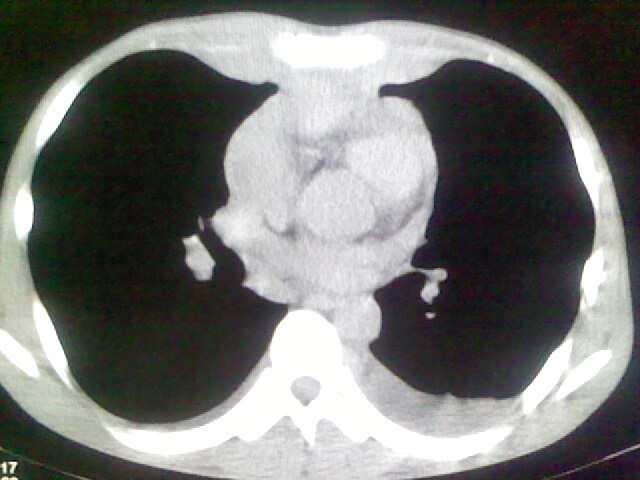

以下是引用杀毒软件在2008-9-3 6:11:00的发言:[br]侵袭性胸腺瘤------一般不侵到气管旁[br][br]考虑----纵隔淋巴瘤,心包及胸膜受累

以下是引用wzr在2008-9-3 5:30:00的发言:[br]侵袭性胸腺瘤

以下是引用随光逐影在2008-9-3 7:07:00的发言:[br]1)考虑淋巴瘤可能。2)双侧胸腔积液(以左侧为甚)。3)心包积液。